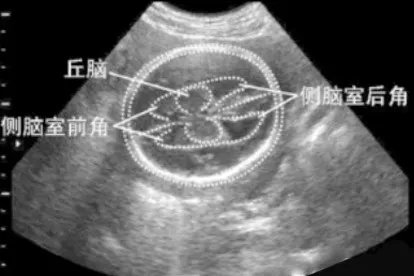

丘脑图注意事项在检查胎儿颅内结构时应该注意大脑半球是否对称,颅内有无局部异常回声过低或过高的回声区,有无异常的液性暗区。

概述正常胎儿颅内结构包括侧脑室、丘脑、中脑、小脑等。位置1.侧脑室:位于大脑半球的深部,左、右各一,呈“C”形室腔,内衬室管膜,腔内充满脑脊液。2.丘脑:是间脑中最大的卵圆形灰质核团,位于第三脑室的两侧,左、右丘脑借灰质团块(称中间块)相连。3.中脑:位于脑桥、小脑和间脑之间,并与它们相连接。4.小脑:位于大脑的后下方,颅后窝内,延髓和脑桥的背面。